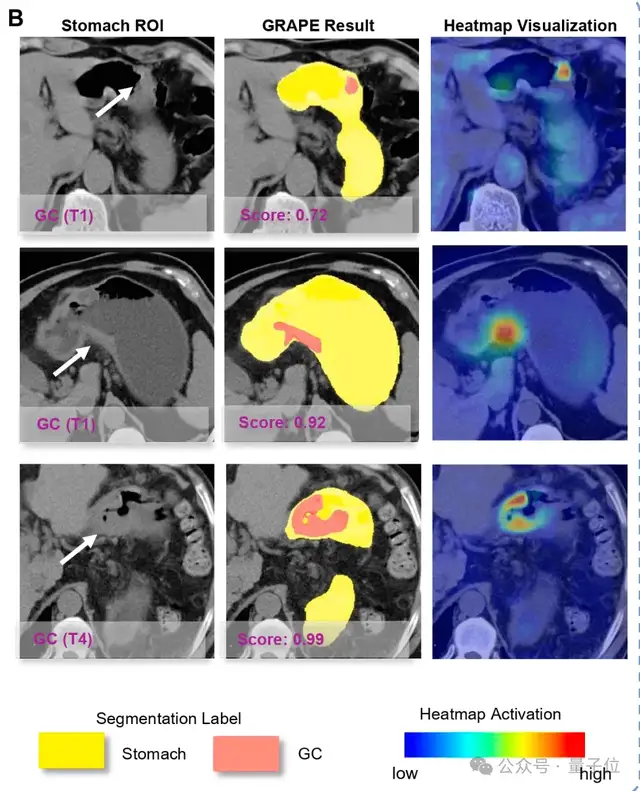

△AI能识别各个阶段的胃癌

DAMO GRAPE的敏感性和特异性分别达到85.1%和96.8%,相比起人类放射科医生分别提升21.8%和14.0%。

△AI成功从平扫CT识别早期胃癌